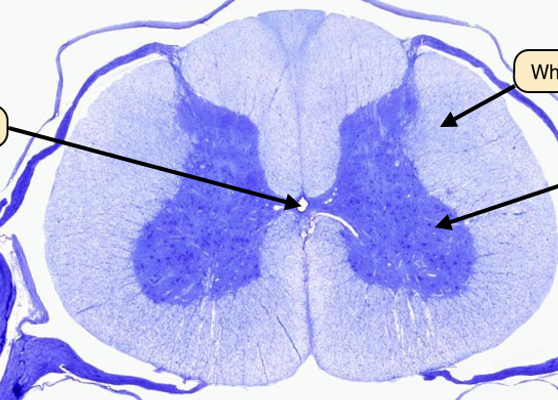

Q

What is the center piece known as

A

central canal